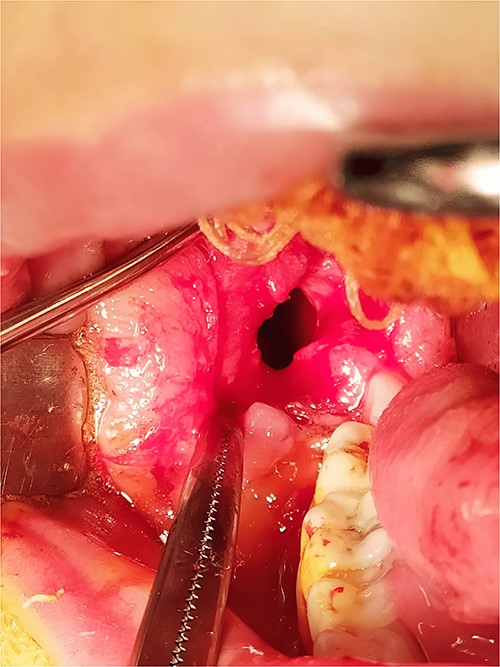

After 12 months, the second stage was performed to remove the lesion (Fig. 6). Under general anesthesia, enucleation with peripheral ostectomy was performed. A flap was developed to expose the anterior border and most of the lateral surface of ramus. The lining of the lesion was detached from the bony walls. A surgical bur was used to remove bone adjacent to the cystic lining. After enucleation, the cavity was filled with gelfoam and the incisions were closed with 4–0 Prolene suture. The patient returned regularly for follow-up after every 3 months (Fig. 7). The total follow-up period so far was 36 months. Cone beam computed tomography (CBCT) scan after 24 and 36 months showed no evidence of lesion recurrence and great bone formation (Fig. 8).

The second stage: (a) surgical exposure of the right anterior border of the ramus. (b) The cystic cavity after the enucleation of the lesion. (c) Removal of the buccal plate to allow access to the entire of the lesion. (d) The cystic cavity after removal of buccal plate and peripheral ostectomy.